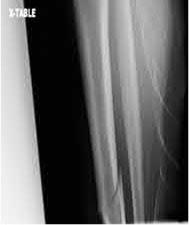

What is the most common type of malalignment after intramedullary nailing of distal 1/3 extra-articular tibia fractures using a infrapatellar approach when compared with plating?

The most common type of malalignment after intramedullary nailing of distal 1/3 extra-articular tibia fractures using an infrapatellar approach when compared with plating is valgus malalignment.

Fixation of distal one-third tibial shaft fractures can be successfully treated with either intramedullary nailing or plating. The literature describes advantages and disadvantages to both approaches, however intramedullary nailing has been shown to lead to increased rates of valgus malunion. Recent studies have shown that using a suprapatellar approach may decrease the incidence of valgus malalignement.

Vallier et al performed a randomized prospective study to compare plate and nail stabilization for distal tibia shaft fractures by assessing complications and secondary procedures. One-hundred and four patients were randomized to either reamed intramedullary nailing, or medial distal tibia plate fixation.

Primary angular malalignment was identified in 17 patients (16.3%). This included four patients treated with tibial plating (8.3%) and 13 patients treated with nails (23%, P = 0.02). Eight of these (7.7% of all patients) had malalignment between 6° and 10° of angulation. Valgus was the most common

angular deformity, accounting for 70% of angular deformity cases.

Avilucea et al. looked at the immediate postoperative alignment of distal tibia fractures (within 5 cm of the tibial plafond) treated with suprapatellar intramedullary nail (IMN) insertion compared with the infrapatellar technique. They found primary angular malalignment of ≥5 degrees occurred in 35 (26.1%) patients with infrapatellar IMN insertion and in 5 (3.8%) patients who underwent suprapatellar IMN insertion. They conclude suprapatellar IMN technique results in a significantly lower rate of malalignment compared with the infrapatellar IMN technique.